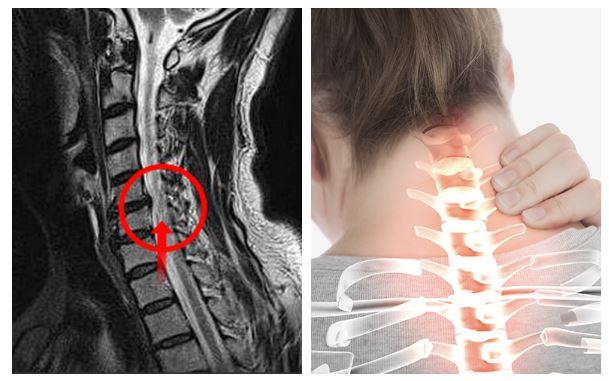

목디스크가 생기면 경추 사이 디스크가 밀려나오며 팔이나 손가락으로 걸치는 신경을 눌러서 억누르게 됩니다 하더라고요. 압박증상으로 말미암아 해당 부위의 감각이 둔해지며 척추가 불안정하게도면 부근에 자리한 관절까지 영향을 미치게 돼 바랍니다. 그러면서 어깨 통증도 나타나게 되지만 이러한 어깨 통증을 느끼시면 오십견 등의 어깨질환과 혼동할 수 있다고 하지만 머리 뒤에 손을 얹는 동작을 하면 통증이 감퇴하는 경우도 있어서 목디스크로 의심을 해보시고 진료를 받아보시는 걸 권장드립니다.

목의 디스크가 손상이 일어나서 부근 신경을 자극하여 심각한 통증을 같이할수 있는데요 통증은 상식적으로 목의 한쪽 면에 유발되며, 어깨나 팔까지 타나날 수 있습니다.